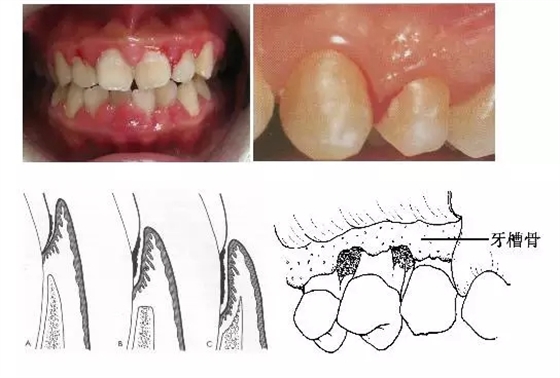

1、牙齦改變:正常牙齦粉紅色、菲薄而緊貼牙面,附著齦有點彩。患牙齦炎時游離齦和齦乳頭呈鮮紅或暗紅色,齦緣變厚,齦乳頭圓鈍,不再緊貼牙面;由于結締組織內炎性浸潤及膠原纖維消失,使原來致密堅韌的牙齦變得松軟脆弱,缺乏彈性;同時由于牙齦腫脹或增生,齦溝深度增加,但上皮附著水平仍位于正常的釉牙骨質界,即出現(xiàn)假牙周袋。

3、牙周袋形成:牙周袋是病理性加深的齦溝,是牙周炎最重要的病理改變之一。按照袋底的位置,可將牙周袋分為骨上袋和骨下袋;按牙周袋累及牙面的情況可將其分為單面袋、復合袋、復雜袋。

4、牙槽骨吸收:牙槽骨吸收是牙周炎的另一個主要病理變化,由于牙槽骨的吸收,使牙齒的支持組織喪失,牙齒逐漸松動,最終脫落或拔除。牙槽骨的吸收可分為水平吸收、垂直吸收、凹坑狀吸收等幾種類型。

5、牙齒松動和移位:由于牙周炎使牙槽骨吸收,牙周支持組織減少是牙齒松動的最主要原因;另外在咬頜創(chuàng)傷合并有牙周炎時,也可造成牙齒松動。由于患有牙周炎的牙齒缺乏牙周支持組織,所以,在咬頜創(chuàng)傷的不良咬頜力作用下,牙齒可出現(xiàn)病理性移位。